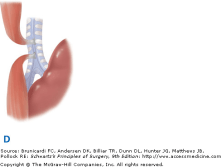

25. Esophageal Atresia and Tracheoesophageal TES:- The most commonly seen variety is EA with distal TEF (type C), which occurs in approximately 85% of the cases in most series. The next most frequent is pure EA (type A), occurring in 8 to 10% of patients, followed by TEF without EA (type E). The latter occurs in 8% of cases and is also referred to as an H-type fistula, based on the anatomic similarity to that letter (Fig. 39-9). EA with fistula between both the proximal and distal ends of the esophagus and trachea (type D) is seen in approximately 2% of cases, and type B, EA with TEF between the proximal esophagus and trachea, is seen in approximately 1% of cases.

The five varieties of esophageal atresia (EA) and tracheoesophageal fistula (TEF). A. Isolated EA.(SECOND MOST COMMON) B. EA with TEF between the proximal segment of the esophagus and the trachea. C. EA with TEF between the distal esophagus and the trachea(MOST COMMMON) D. EA with fistula between both the proximal and distal ends of the esophagus and the trachea. E. TEF without EA (H-type fistula).(THIRD MOST COMMON)